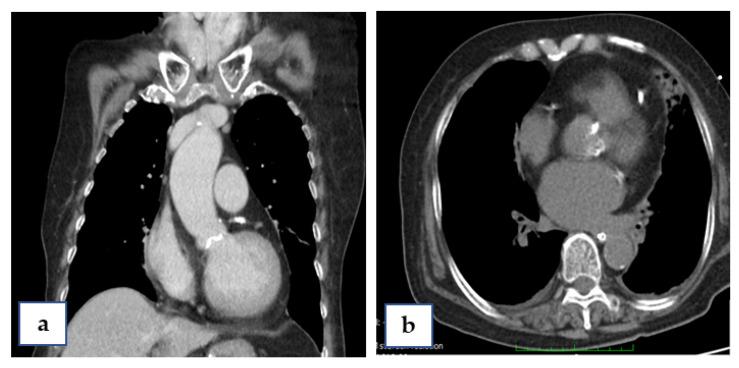

Transcatheter aortic valve implantation (TAVI) has evolved to be the treatment of choice for patients with severe aortic stenosis and high perioperative risk. Cardiogenic shock is one of the most severe complications during the TAVI procedure, especially as the prognosis of cardiogenic shock secondary to aortic stenosis is very poor. This situation can be challenging, while extracorporeal membranous oxygenation (ECMO) can be a treatment option. Here, we reported on an 88-year-old female patient who had been diagnosed as non-ST-elevation myocardial infarction (NSTEMI) and critical aortic valve stenosis (AS) with a logistic Euroscore of 25%. Percutaneous coronary angioplasty (PCI) was performed smoothly and developed tachy-brady arrhythmia of atrial fibrillation then cardiac arrest at the beginning of the TAVI procedure. A v-a ECMO was installed at her left femoral side. Afterward, the TAVI procedure was completed accordingly; her consciousness recovered and Levosimendan therapy enhanced her left-ventricular ejection fraction (LVEF) from 22% to 40%. Five days after TAVI, ECMO was replaced by intra-aortic balloon pumping (IABP) and it was removed 3 days later. A minor complication of this therapy, e.g., muscular weakness in her left leg, was noted. The patient underwent rehabilitation for about 2 months, and was discharged from hospital with a wheel chair and clear consciousness. At the 24 month follow-up she was in good recovery and was able to walk upstairs to the second floor again. Our experience suggests that one indication of prophylactic use of ECMO is for patients with an unstable hemodynamic condition.

经导管主动脉瓣植入术(TAVI)已成为严重主动脉瓣狭窄和围手术期高风险患者的首选治疗方法。心源性休克是 TAVI 过程中最严重的并发症之一,尤其是继发于主动脉瓣狭窄的心源性休克预后极差。这种情况可能具有挑战性,而体外膜肺氧合(ECMO)可以作为一种治疗选择。在这里,我们报告了一位 88 岁女性患者的病例,该患者被诊断为非 ST 段抬高型心肌梗死(NSTEMI)和严重的主动脉瓣狭窄(AS),Logistic Euroscore 为 25%。经皮冠状动脉介入治疗(PCI)顺利进行,在 TAVI 手术开始时出现心动过速-心动过缓性房颤伴快速性心律失常,继而发生心脏骤停。在她的左股侧安装了 v-a ECMO。此后,相应地完成了 TAVI 手术;她的意识恢复,左心室射血分数(LVEF)从 22%提高到 40%。TAVI 后 5 天,ECMO 被主动脉内球囊反搏(IABP)取代,3 天后被移除。该治疗方法的一个轻微并发症是她左腿肌肉无力。患者接受了大约 2 个月的康复治疗,出院时乘坐轮椅,意识清醒。在 24 个月的随访中,她恢复良好,能够再次走上二楼。我们的经验表明,预防性使用 ECMO 的一个适应证是对血流动力学不稳定的患者。